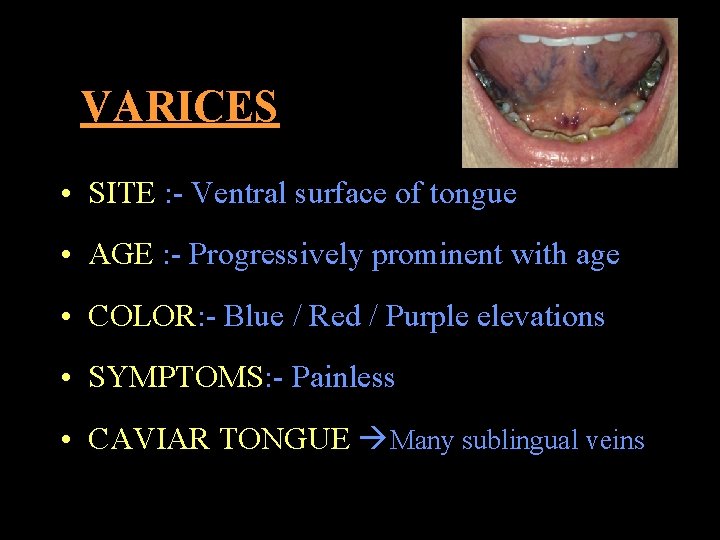

VARICES • SITE : - Ventral surface of tongue • AGE : - Progressively prominent with age • COLOR: - Blue / Red / Purple elevations • SYMPTOMS: - Painless • CAVIAR TONGUE Many sublingual veins